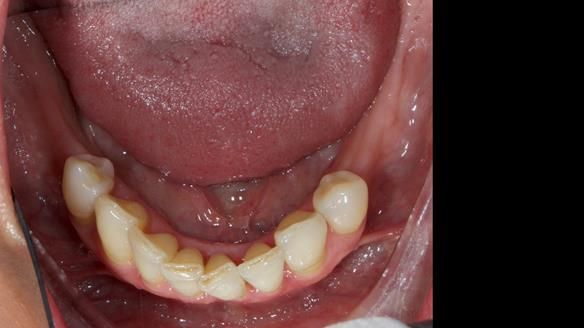

We provided her with an immediate upper denture (Mk 1), followed by a definitive metal-based upper denture (Mk 2). A lower removable partial denture was discussed, to be made only if needed once the upper treatment was complete. However, at review, this wasn’t necessary — Adnana had excellent neuromuscular control and function, even with a shortened dental arch (SDA).